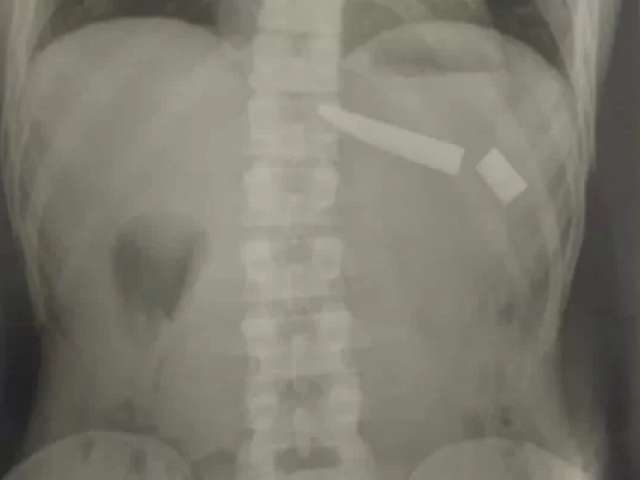

Faca quebra dentro do tórax de homem durante briga com vizinho em GO